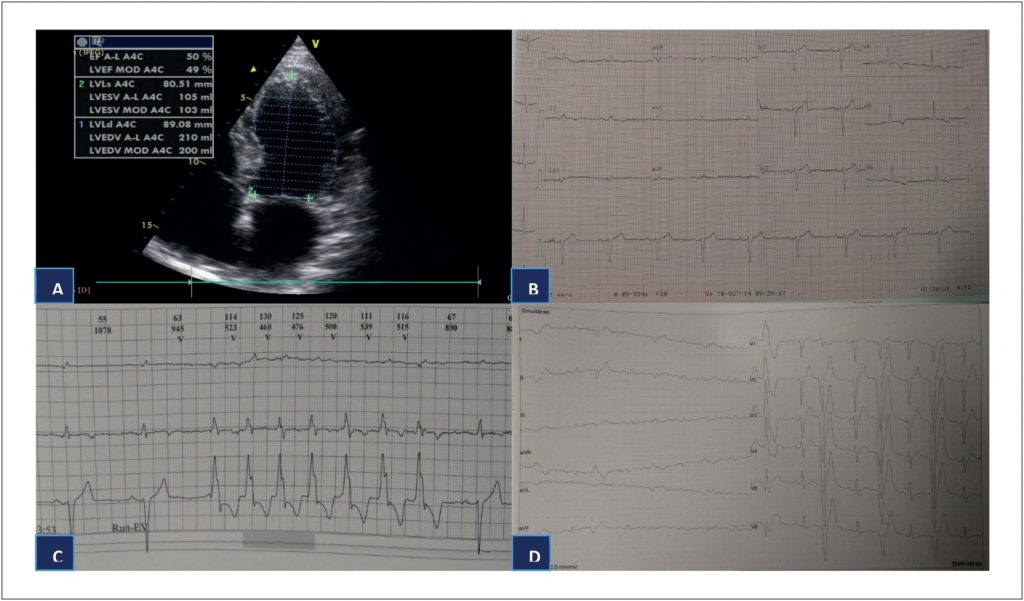

Nova Mutação no Gene DSP – Um Caso de Cardiomiopatia Arritmogênica com Fenótipo Isolado do Ventrículo Esquerdo e Alto Risco de Morte Súbita

A morte súbita cardíaca (MSC) em adultos jovens (18–35 anos) é causada mais frequentemente de cardiomiopatias hereditárias previamente não diagnosticadas. As causas mais comuns de MSC são a cardiomiopatia hipertrófica e a cardiomiopatia arritmogênica (CMA), seguidas de anomalias congênitas das artérias coronárias, miocardite, ruptura aórtica na síndrome de Marfan, defeitos de condução, e doenças valvulares.

A CMA é responsável por até 20% dos casos de MSC em indivíduos abaixo dos 35 anos de idade. Em uma série de 86 vítimas jovens de MSC, a CMA representou 10,3% dos casos, sendo a segunda maior causa de MSC. A cardiomiopatia dilatada (CMD) é uma causa menos frequente de MSC entre jovens, representando aproximadamente 2% dos casos em atletas.